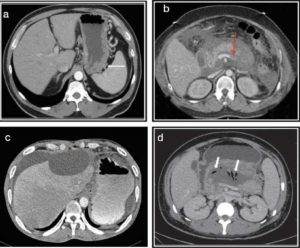

Іншими словами, МРТ можливо як при наявності вже підтвердженого діагнозу для уточнення поточного стану органу, так і в якості діагностичної заходи, коли діагноз ще не встановлений. У всіх цих випадках слід виконати МРТ підшлункової залози – з контрастом або без такого, як порекомендує лікар. Відзначимо, що в обох випадках точність дослідження досить висока, проте контраст дозволяє побачити новоутворення розміром менше двох міліметрів, в той час як обстеження без контрасту «покаже» лише зміни більшого масштабу.